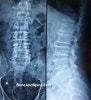

(1) X-ray

① 퇴행성 질환소견 : 추간판 공간감소, 골증식체(osteophyte), 인대골극 형성, 척추후관절의 비대, 척추후관절의 연골공간 감소

② 퇴행성 과정 진행에 따라 종판이 인접한 곳에 반응성 골 형성이 나타납니다. 드물게는 이런 경화성 반응이 뚜렷하여 특발성 척추 과골화증을 초래합니다.

③ 남성 < 여성에게 흔하고, L4 추체의 하연에 선택적으로 나타나는 것처럼 보입니다.

X-ray : 요추 척추증(Lumbar spondylosis)